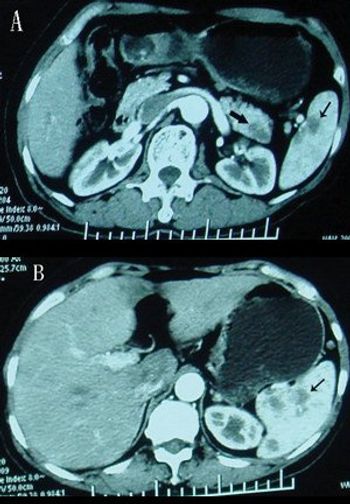

Pancreatic cancer patients with long-standing diabetes have poorer survival than those without diabetes, according to an analysis of a pair of studies.

About 9% of pancreatic cancer cases appear to be familial, and the risk of cancer in relatives of these patients does not appear limited to the pancreas.